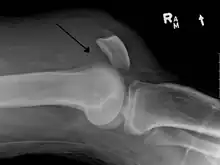

Quadriceps tendon rupture in plain X-ray

X-ray of a tear of the patellar tendon. On the left: The kneecap is pulled up. On the right: Significant dent in the soft tissue above the kneecap.